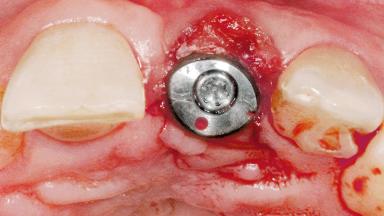

Late Flapless Placement of an Implant in a Maxillary Left Central Incisor Site

A 39-year-old male patient presented with a chief complaint of discomfort and gingival discoloration around his maxillary left central incisor. He was in good general health and was a non-smoker. His past dental history was significant because of the traumatic fracture of tooth 21 in a sporting accident at age 13. Initial dental treatment included endodontic therapy and a full-coverage restoration. The patient became symptomatic 5 years later, when structural failure of the tooth resulted in the dislodgment of the crown. Endodontic retreatment, apical surgery, and post-and-core restoration were performed.

Bone Augmentation Horizontal|Staged

Augmentation Materials Xenogenous|Membrane

Bone Volume Deficient horizontally, requiring prior grafting